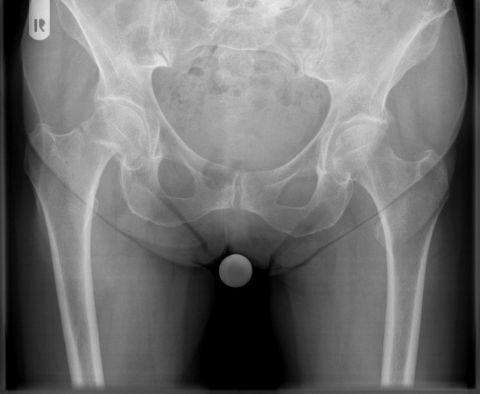

03/2021 – 76 jährige Frau mit wahrscheinlich durch Osteoporose bedingtem Bruch des Schenkelhalses rechts. Es wurde ein zementierter Standardschaft verwendet, der eine gleichmäßige Krafteinleitung in den Knochen des Oberschenkels gewährleistet.  Verlauf sonst unkompliziert mit guter Gelenkfunktion bereits 2 Monate nach Operation. Die Osteoporose sollte durch Bewegung und Medikamente über einen längeren Zeitraum behandelt werden.

rechtsseitige Schenkelhalsfraktur